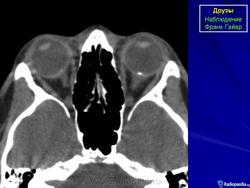

При КТ-исследовании изредка попадаются больные с наличием у них в области диска зрительного нерва плотных включений, которые могут быть приняты за инородные тела. Это так называемые друзы. Друзы диска зрительного нерва – довольно редкое заболевание, характеризующееся гроздевидными округлыми возвышениями над диском нерва, состоящими из гиалина. Иногда в них откладывается известь. Считают, что друзы имеют наследственный характер.

КТ-семиотика

При КТ друзы отличаются локализацией – только в диске зрительного нерва, небольших размеров (не более одного миллиметра) и правильной округлой формы. Друзы совершенно однородны, не дают артефактов и имеют определенную плотность (150-200 НU).